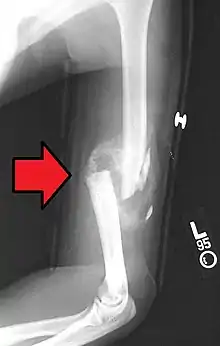

| Midshaft humerus fracture with callus formation | |

A transverse fracture of the humerus shaft